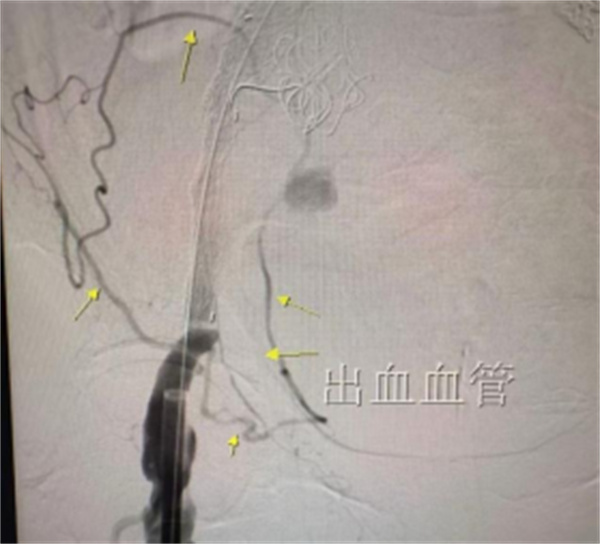

在患者经由急诊绿色通道直送导管室后,由杨永久、丁旭、郑新颖以及导管室技师护士组成的治疗团队随机开始急诊抢救手术。术中,患者仅能在高剂量血管活性药物支持下将血压维持在100mmHg左右,手术操作难度大。团队依次完成病变血管评估、髂内动脉栓塞、支架主体及髪支支架植入。术中探查发现,患者除主髂动脉瘤破裂出血外,腹壁下动脉和旋髂浅动脉仍在持续向右侧破裂的髂动脉瘤腔供血,属隐蔽性出血源。杨永久果断采用微导管超选择技术,精确定位并封堵两支出血血管,完成主髂动脉腔内隔绝治疗。